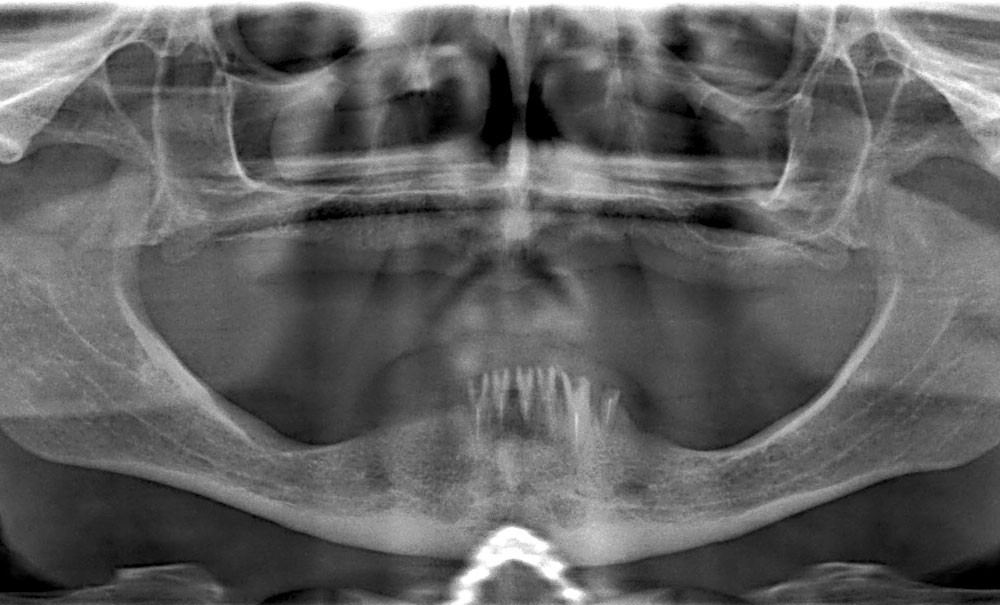

La perte des dents s’accompagne toujours d’une résorption osseuse plus ou moins importante, phénomène parfois accentué par le port de prothèses amovibles qui peuvent se révéler iatrogènes et accroître la perte osseuse. La classification de Bedrossian [1] divise le maxillaire supérieur en trois zones (fig. 1) :

La présence d’os dans les trois zones autorise une distribution idéale des implants avec notamment l’absence de cantilever. Quand l’os est absent ou en faible quantité dans la zone 3, le recours à l’angulation des implants distaux le long du mur antérieur des sinus est possible ; le cas peut alors être traité selon la technique « All-on-four ». En revanche, quand le seul volume osseux disponible est en zone 1, le recours à des implants transzygomatiques (ou à des greffes osseuses) est indispensable [2].